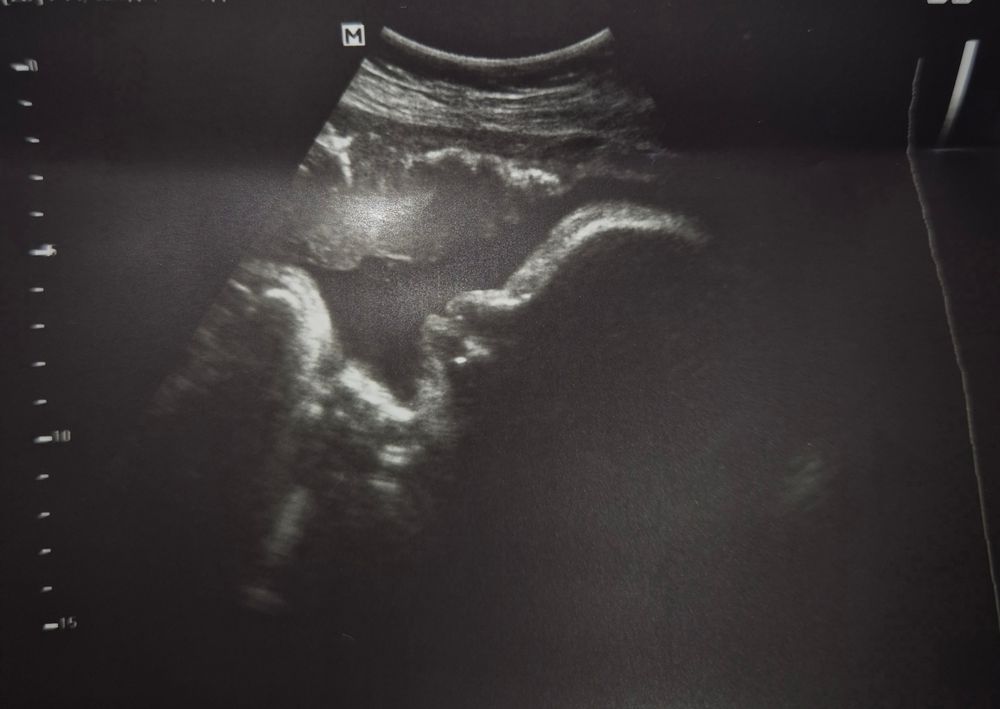

38 недель 💝